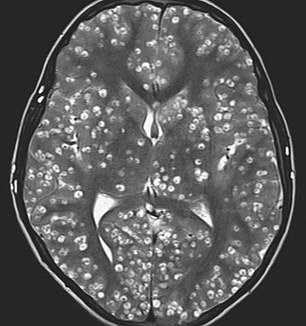

In the MRI scan, you can see the young man’s brain. The damage that the pork-based parasite caused is consistent with neurocysticercosis, which is extremely dangerous and deadly in many cases. The condition occurs when parasitic larvae bust into the brain after you eat under-cooked pork products. These larvae hole up inside your body until they’re strong enough to invade your nervous system and travel to your brain.

Take a look at the brain scans. Do you see those white spots? Well, those are the parasites invading the Indian boy’s brain.

Cysts were discovered along the man’s cerebral cortex. This is an essential part of the brain. It rules our thinking and information processing. The parasites were so ingrained in the man’s brain that they were affecting his ability to use his five senses.